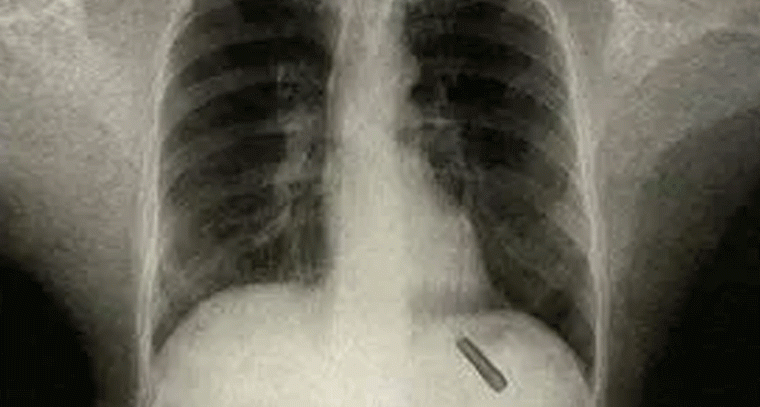

26 ఏళ్లుగా ఊపిరితిత్తుల్లో పెన్ క్యాప్.. వైద్యులను ఆశ్చర్యపరిచిన ఘటన!

ఓ వ్యక్తి చిన్ననాట పొరపాటున పెన్ క్యాప్ మింగేశాడు. ఆ ప్లాస్టిక్ క్యాప్ ఏకంగా 26 ఏళ్ల పాటు అతడి ఊపిరితిత్తుల్లోనే ఉండిపోయింది. తాజాగా ఢిల్లీలోని వైద్యులు శస్త్రచికిత్స చేసి ఆ పెన్ క్యాప్‌ను విజయవంతంగా తొలగించారు.వివరాల్లోకి వెళితే.. ఢిల్లీకి చెందిన వ్యక్తి ఏడేళ్ల వయసులో ఆడుకుంటూ ఉండగా ప్లాస్టిక్ పెన్ క్యాప్ మింగేశాడు. అయితే ఆ విషయాన్ని తల్లిదండ్రులకు చెప్పలేదు. ఆశ్చర్యకరంగా, అంత కాలం అతనికి పెద్దగా ఎలాంటి ఇబ్బంది లేకుండా గడిచిపోయింది.కానీ గత కొన్ని రోజులుగా అతనికి తరచుగా దగ్గు రావడం, దగ్గుతున్నప్పుడు రక్తం రావడం ప్రారంభమైంది. దీంతో ఆందోళన చెందిన అతను ఆస్పత్రిని ఆశ్రయించాడు. వైద్యులు స్కాన్‌లు చేసి పరిశీలించగా, అతడి ఊపిరితిత్తుల్లో ఒక వస్తువు ఇరుక్కుపోయినట్టు గుర్తించారు. అది అలాగే ఉంటే ప్రాణాపాయం తప్పదని భావించి శస్త్రచికిత్స చేశారు. ఆపరేషన్ సక్సెస్ కావడంతో, డాక్టర్లు ప్లాస్టిక్ పెన్ క్యాప్‌ను బయటకు తీశారు.ఈ విషయం తెలుసుకున్న వైద్యులు కూడా ఆశ్చర్యపోయారు. శస్త్రచికిత్స చేసిన డాక్టర్ రోమన్ దత్తా మాట్లాడుతూ.. “ఒక వస్తువు ఇంతకాలం ఊపిరితిత్తుల్లో ఉండటం చాలా అరుదైన విషయం. సాధారణంగా ఇలాంటి సందర్భాల్లో తీవ్ర ఇన్ఫెక్షన్లు లేదా ప్రాణహాని వచ్చే ప్రమాదం ఉంటుంది. ఈ వ్యక్తి ఇంతకాలం బాగానే ఉండటం నిజంగా అసాధారణం” అని చెప్పారు.ప్రస్తుతం ఆ వ్యక్తి ఆరోగ్యం నిలకడగా ఉందని వైద్యులు తెలిపారు. “ఎవరైనా ఏదైనా వస్తువును మింగినప్పుడు వెంటనే ఆస్పత్రికి తీసుకెళ్లాలి. ముఖ్యంగా పిల్లల విషయంలో ఆలస్యం చేయకూడదు. లేదంటే భవిష్యత్తులో తీవ్ర సమస్యలు తలెత్తే అవకాశముంది” అని సూచించారు.